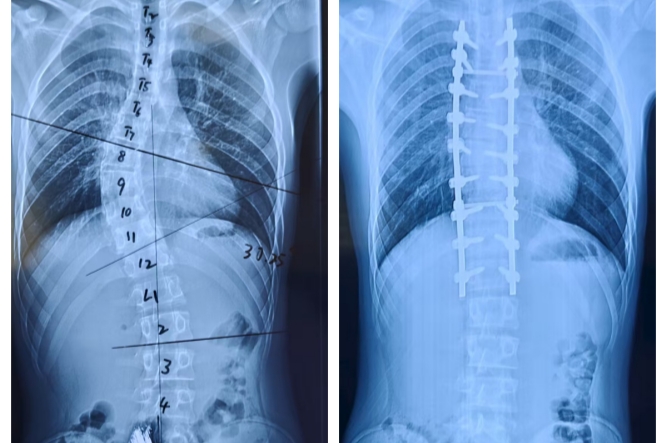

晉城大醫(yī)院再次成功為藏族少年實(shí)施高難度脊柱側(cè)彎矯正手術(shù)

15歲藏族少年小卓跨越千里,到晉城大醫(yī)院進(jìn)行“脊柱側(cè)彎矯正手術(shù)”治療。

陽光少年彎曲的脊柱回歸正道,身高增長(zhǎng)了7厘米,他挺直腰板,康復(fù)出院啦。

近日,來自青海玉樹患有嚴(yán)重脊柱側(cè)彎合并脊髓空洞癥的15歲藏族少年小卓(化名),在晉城大醫(yī)院多學(xué)科團(tuán)隊(duì)的協(xié)作下,成功接受了高難度的脊柱截骨矯正手術(shù),挺直腰桿,重獲新生。、

入院后,脊柱骨科團(tuán)隊(duì)立即為小卓進(jìn)行了全面的術(shù)前檢查。各項(xiàng)檢查結(jié)果均顯示:先天性脊柱側(cè)彎、脊髓空洞、骶1隱性裂。

骨科、心血管內(nèi)科、呼吸與危重癥醫(yī)學(xué)科、麻醉科、臨床營養(yǎng)科等多學(xué)科會(huì)診,制定周密的治療方案:一是小卓需進(jìn)行頸頜吊帶+骨盆牽引,糾正一定的畸形角度;二是針對(duì)小卓BMI偏低的情況定制科學(xué)食譜,為手術(shù)筑牢營養(yǎng)關(guān);三是實(shí)施脊柱截骨矯正手術(shù)+內(nèi)固定術(shù)。

經(jīng)過7個(gè)小時(shí)的手術(shù),手術(shù)成功完成。術(shù)后醫(yī)護(hù)團(tuán)隊(duì)24小時(shí)密切監(jiān)護(hù)小卓的恢復(fù)情況,術(shù)后康復(fù)治療對(duì)于脊柱功能的全面恢復(fù)至關(guān)重要,康復(fù)師第一時(shí)間為小卓進(jìn)行功能康復(fù)鍛煉。

經(jīng)過16天的精心治療,小卓的脊柱外觀明顯改善,實(shí)現(xiàn)了真正的脫胎換骨,康復(fù)出院。